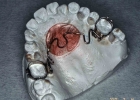

ナンスのホールディングアーチ

製作したナンス

製作したナンス 口腔内にセット

口腔内にセット

構造

パラータルバーと似たような構造ですが、500円玉大の円盤状のパットが、つかえ棒のように張り付いて、奥歯が前にズレて来ないよう押さえるような構造になっています。パラータルバーと同じで、左の図のように、石膏模型上で製作します。

装置使用の目的

マルチブラケット装置や上顎前方牽引装置を使用するときの土台(固定源)として上顎の裏側に装着します。とくに歯の本数を減らしてマルチブラケット装置を付けるような症例の場合、奥歯が抜歯した隙間に寄りすぎると、凸凹をきちんと平らにできなくなったり、前歯が十分に引っ込められなくなったりします。そこで、奥歯が不用意に位置を変えないよう、きちんと固定させるために用います(加強固定)。

マルチブラケット装置と併用する場合、治療期間の大体半分くらい継続して付けておきますが、治療後半には時期を見て撤去します。